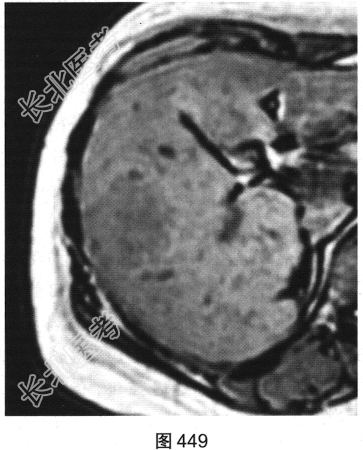

- 多项选择题3.[提示]随后患者接受上腹部MRI检查,如图449~图452所示。对患者MRI检查图像描述不正确的是( )

A、纤维瘢痕呈延迟强化

B、门静脉期病灶轻度强化

C、T1WI示病灶为稍低信号

D、动脉期病灶明显强化

E、T2WI示病灶为稍高信号

F、病灶内无纤维瘢痕